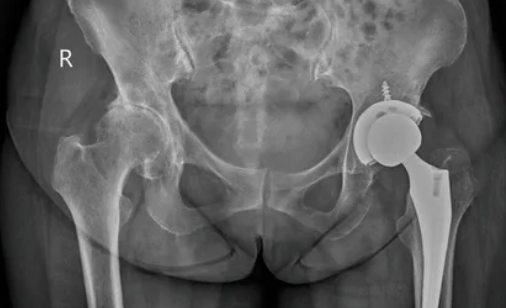

① 고관절 인공관절 치환술 (전체 치환)

가장 많이 시행되는 수술입니다.

손상된 고관절을 제거하고

인공관절로 완전히 바꾸는 방식입니다.

고령자, 중증 관절염 환자에게

가장 흔히 시행됩니다.